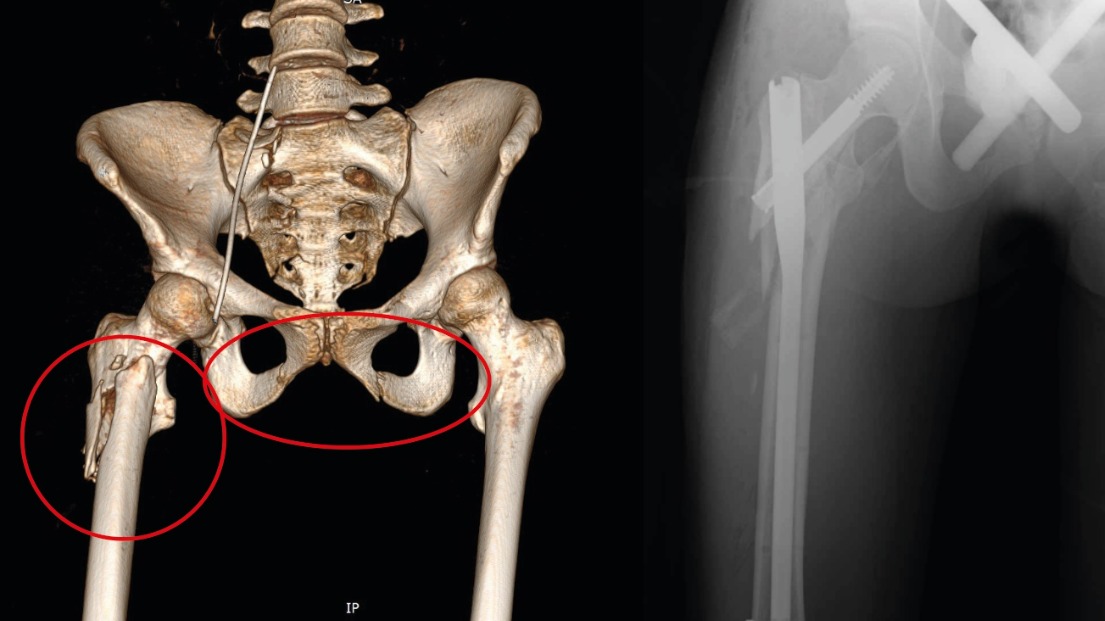

В подмосковном Сергиевом Посаде 18-летняя девушка выжила после падения с девятого этажа. Доктора диагностировали у нее черепно-мозговую травму, закрытое повреждение грудной клетки с поражением легких, а также переломы костей таза и бедра и травму живота. Об этом в четверг, 25 сентября, сообщили в пресс-службе Сергиево-Посадской больницы.

После прибытия в медучреждение пострадавшую в крайне тяжелом состоянии сразу же направили в реанимацию — она потеряла много крови и находилась в коме. Медики оперативно начали переливание, ввели антибиотики, дренировали легкие и наложили аппараты внешней фиксации на переломы. Уже через несколько дней девушка пришла в себя, а спустя еще две недели она смогла отправиться домой.